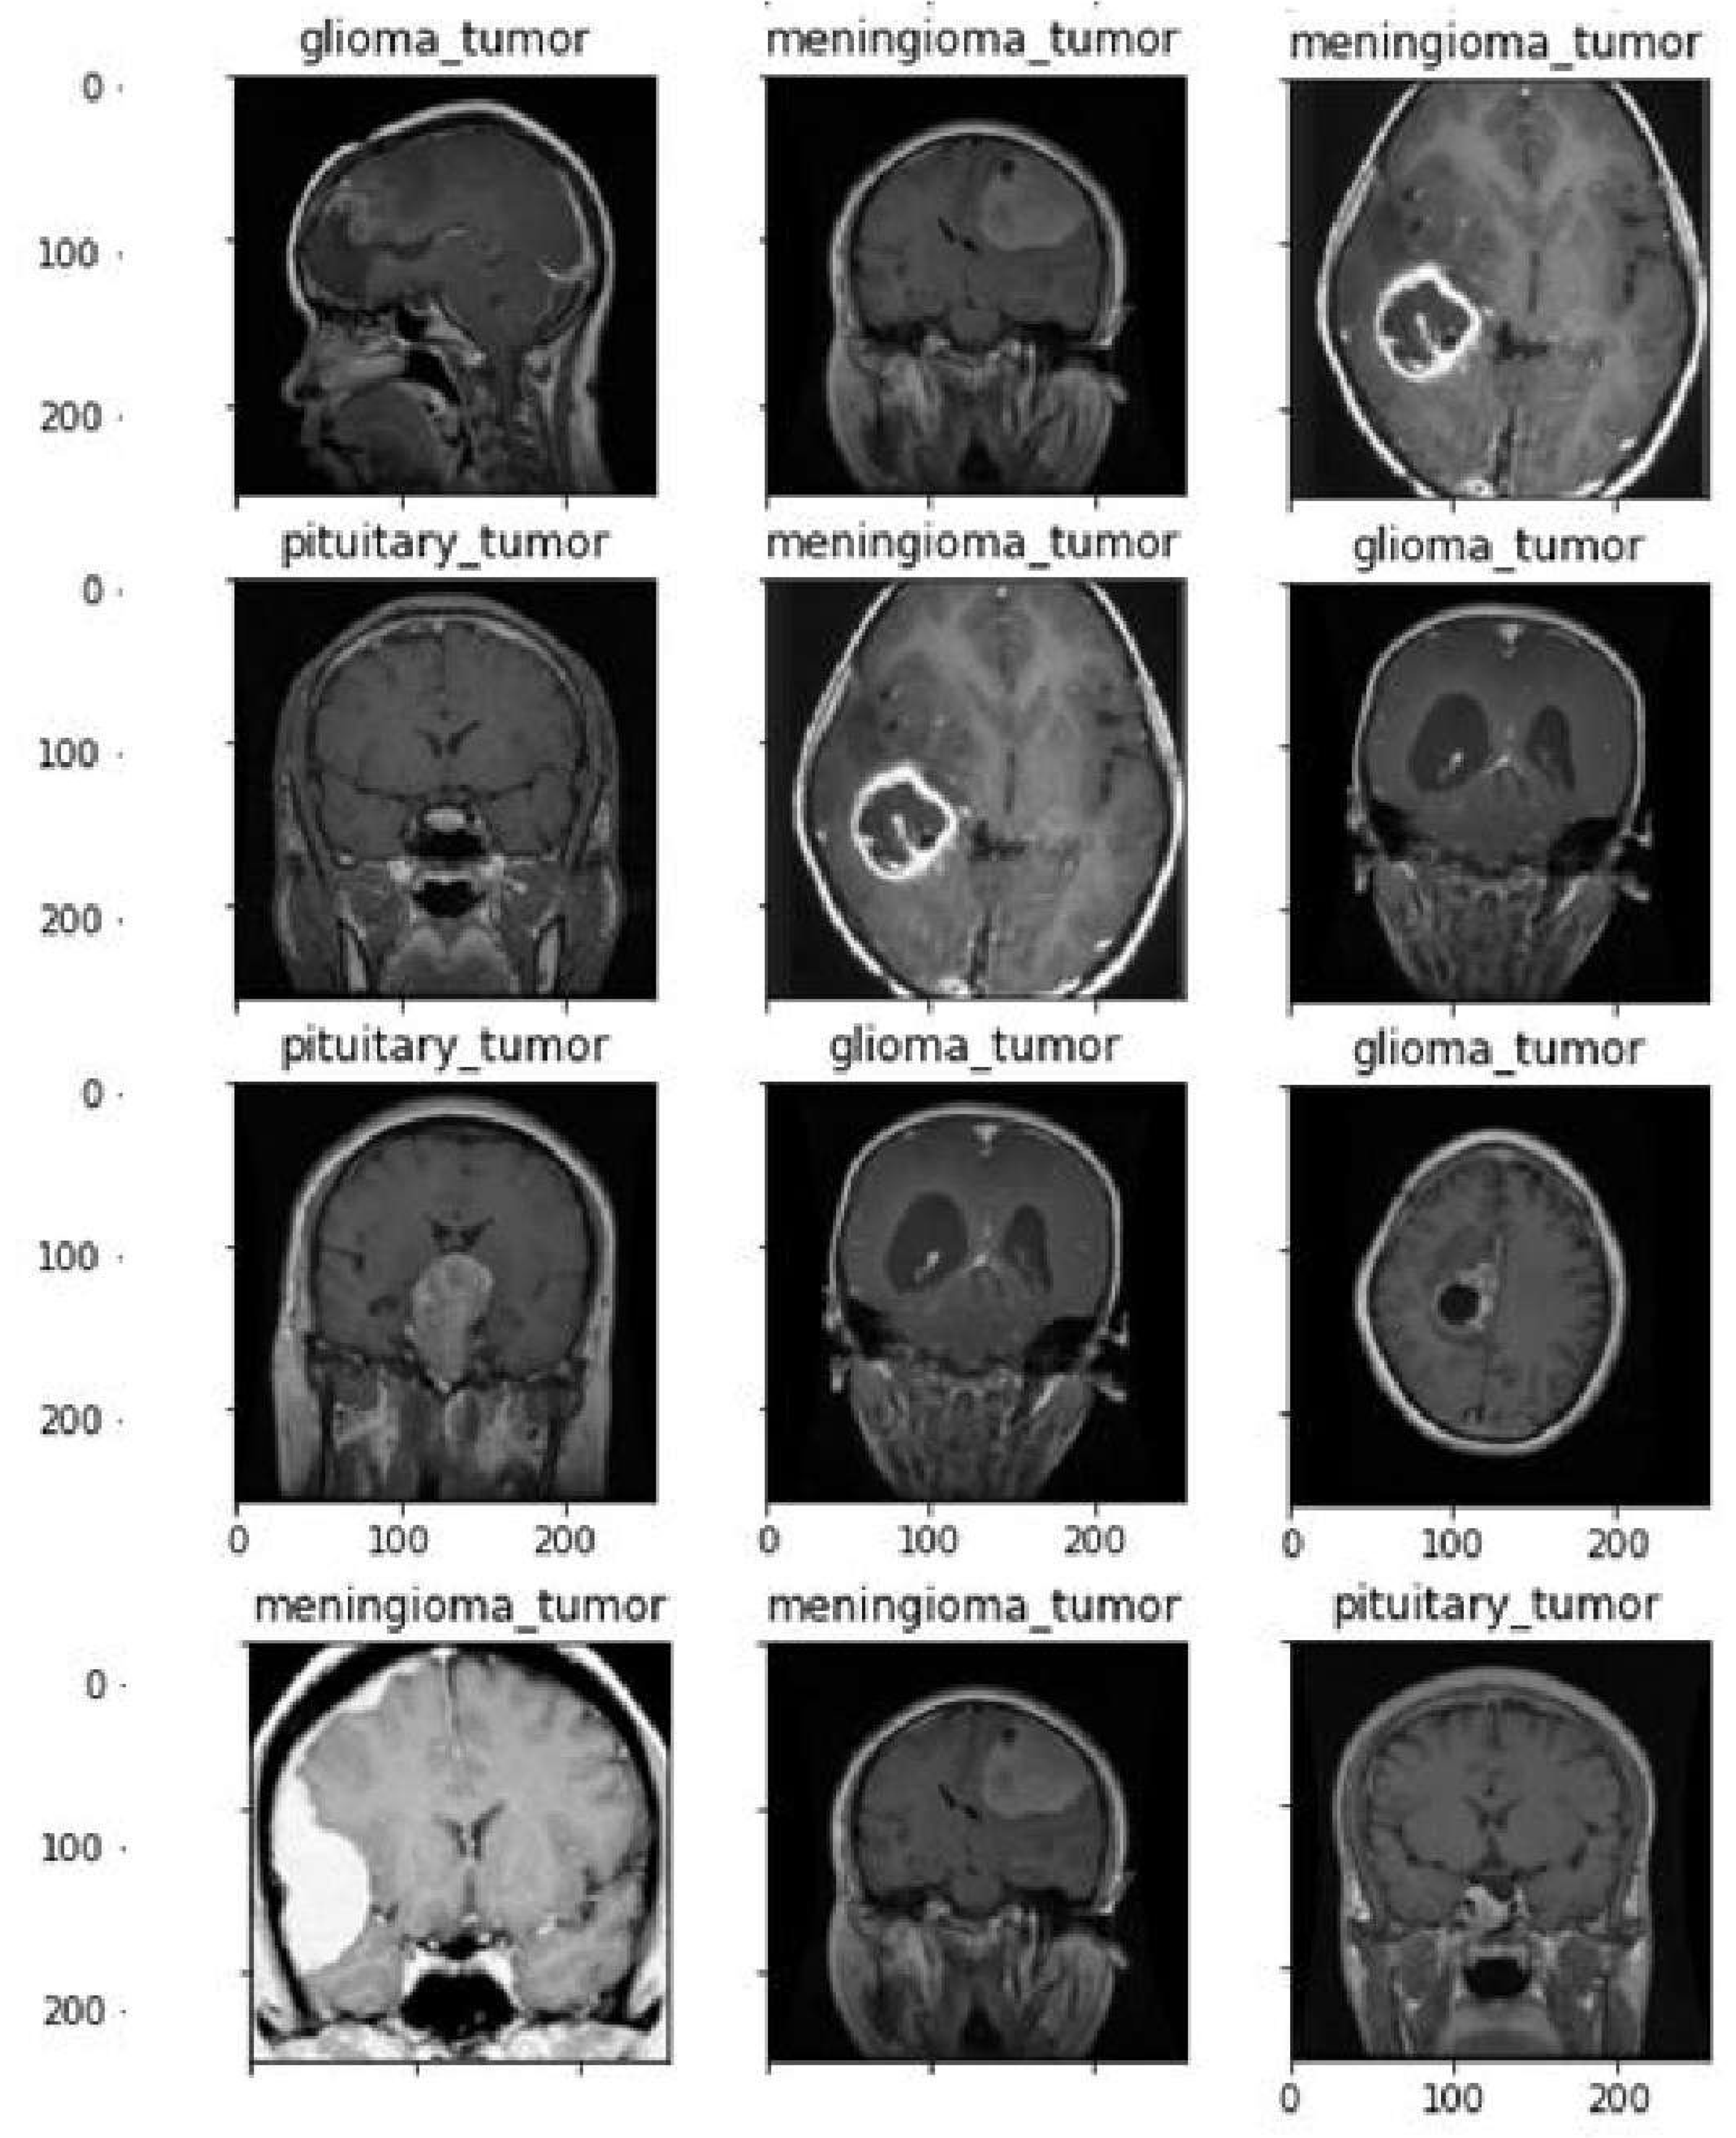

4.2. Dataset

| 1 | figshare.com/articles/brain_tumour_dataset/1512427/5) |